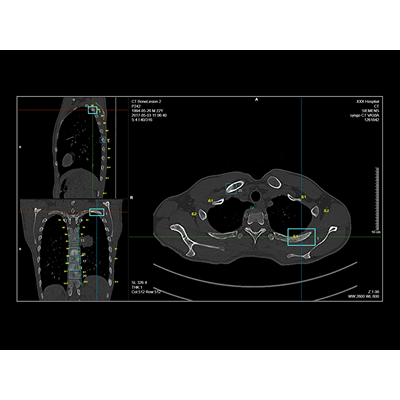

联影智能CT骨转移智能分析系统可秒级检出及分类原发骨肿瘤、溶骨性骨转移、成骨性骨转移、混合型骨转移与其他骨异常病灶,同时精准标识肋骨、椎体、盆骨位置,自动提供病灶定位信息,系统支持MPR三视图同步对比阅片、一键归档PACS功能,辅助医生高效、精准地完成肋骨、椎骨与盆骨骨疾病的诊断,避免漏诊。

联影智能CT骨转移智能分析系统支持多部位、多病灶类型的智能检出,自动标记骨头及定位病灶,极大降低了漏诊概率。其智能随访功能能自动精准配准图像,协助医生高效评估病情发展。系统还支持手动新增和编辑病灶,以及自动生成检查所见,有效提升了医生的工作效率和诊断准确性,为骨转移瘤的精准诊疗提供了强有力的支持。